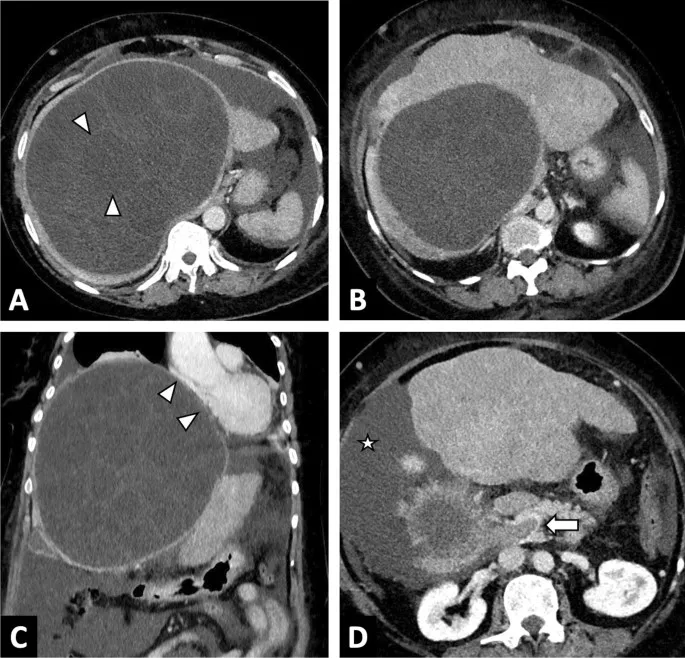

- Forms unilocular hydatid cysts, often large. Sites: Liver (~70%), lungs (~20%).

- Cyst: Inner germinal layer (protoscolices, daughter cysts), outer laminated layer. Host forms pericyst.

- Diagnosis: Imaging (USG/CT), serology. WHO staging guides therapy.

⭐ "Hydatid sand" (free protoscolices in cyst fluid) is a key diagnostic finding.